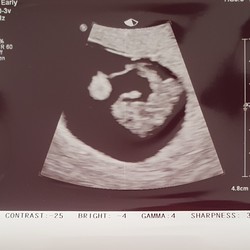

Ik dacht 7+3 te zijn gisteren. Kindje was op de echo 1,5cm groot. Op basis daarvan werd ik een beetje vooruit gezet en 7+6 geschat

Ik was gemeten op precies 8 weken. En mijn vruchtje was 1.67 cm

Nu konden ze het nog niet precies zeggen. Dus over 2 weken terug

Hei daar heb ik nog nooit van gehoord had de echo van me schoonzus ook gezien op zelfde weken die had een hele andere maat. Ik zit op 8+3 op de echo. Ik ga het eens mijn verloskundige vragen want zie ook hier op topics andere mm ben wel benieuwd

Ze kunnen het precies zeggen rond de 11 weken. Elke mm kan zo maar 茅茅n dag langer of korter zijn.